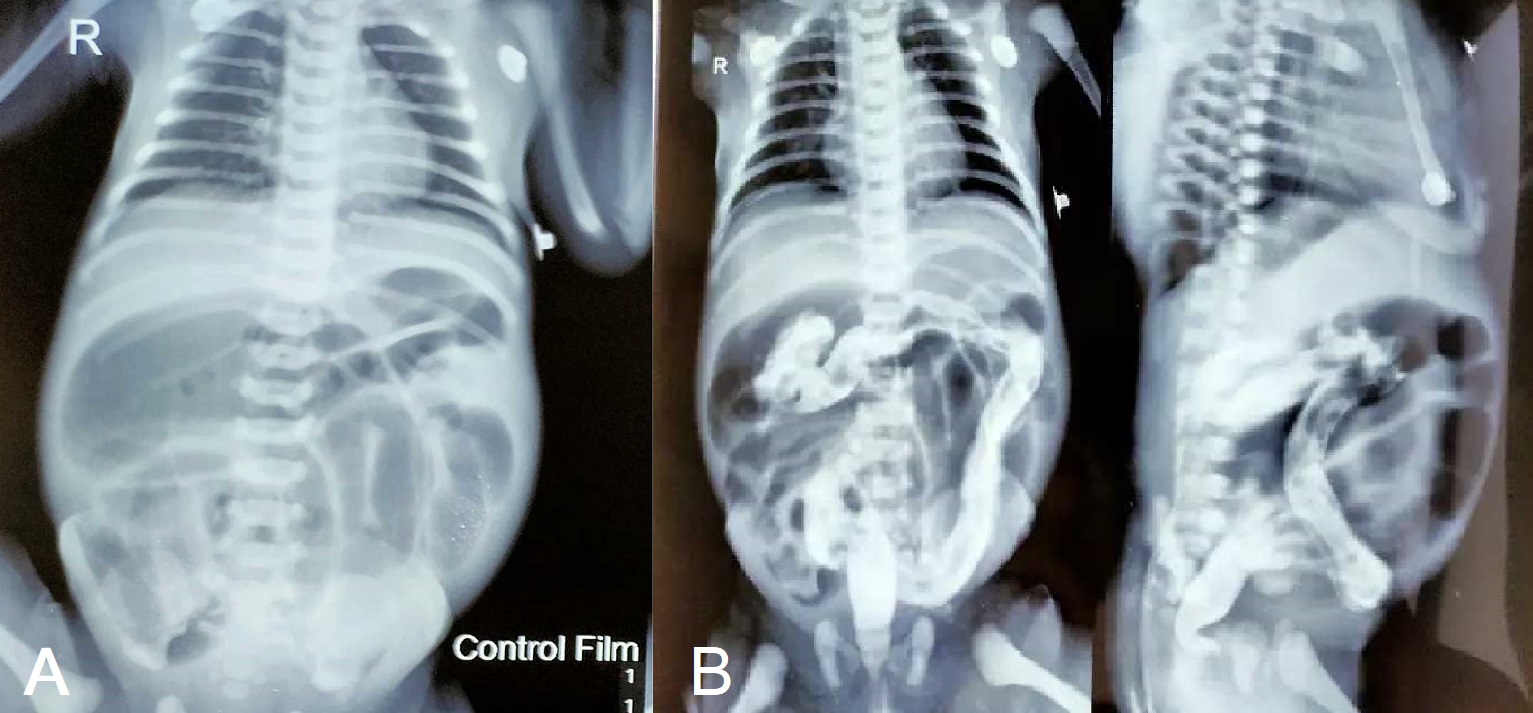

A full-term,3-day-old male baby presented with failure to pass meconium since birth, along with abdominal distension and bilious vomiting. Antenatal period was uneventful and he wasdelivered normally. At the time of admission, patient had features of some dehydration. Vital signs were stable. Abdominal examination revealed tense, distended abdomen with exaggerated bowel soundsand no palpable lump. Hernial orifices were intact. Perineal examination revealed normal positioned anal opening and well-formed external genitalia. After rectal stimulation, patient passed scanty amount of meconium. His biochemical parameters were within normal range except for mild hyponatremia (Hb: 16.9 g/dl; Platelets: 200,000 /cumm; WBC: 8,200 /cumm; Creatinine: 0.7; Sodium: 132 mmol/L; Potassium: 4.5 mmol/L, Total Bilirubin: 1.8 mg/dl; CRP: 12mg/L). Ultrasound of whole abdomen revealed normal scan. Water soluble contrast enema revealed normal looking colon with dilated small bowels suggesting small bowel obstruction (Fig. 1).

Figure 1

A) Hugely dilated small bowel; B)1-hour post water soluble contrast enema showing normal shape colon and contrast reaching caecum.